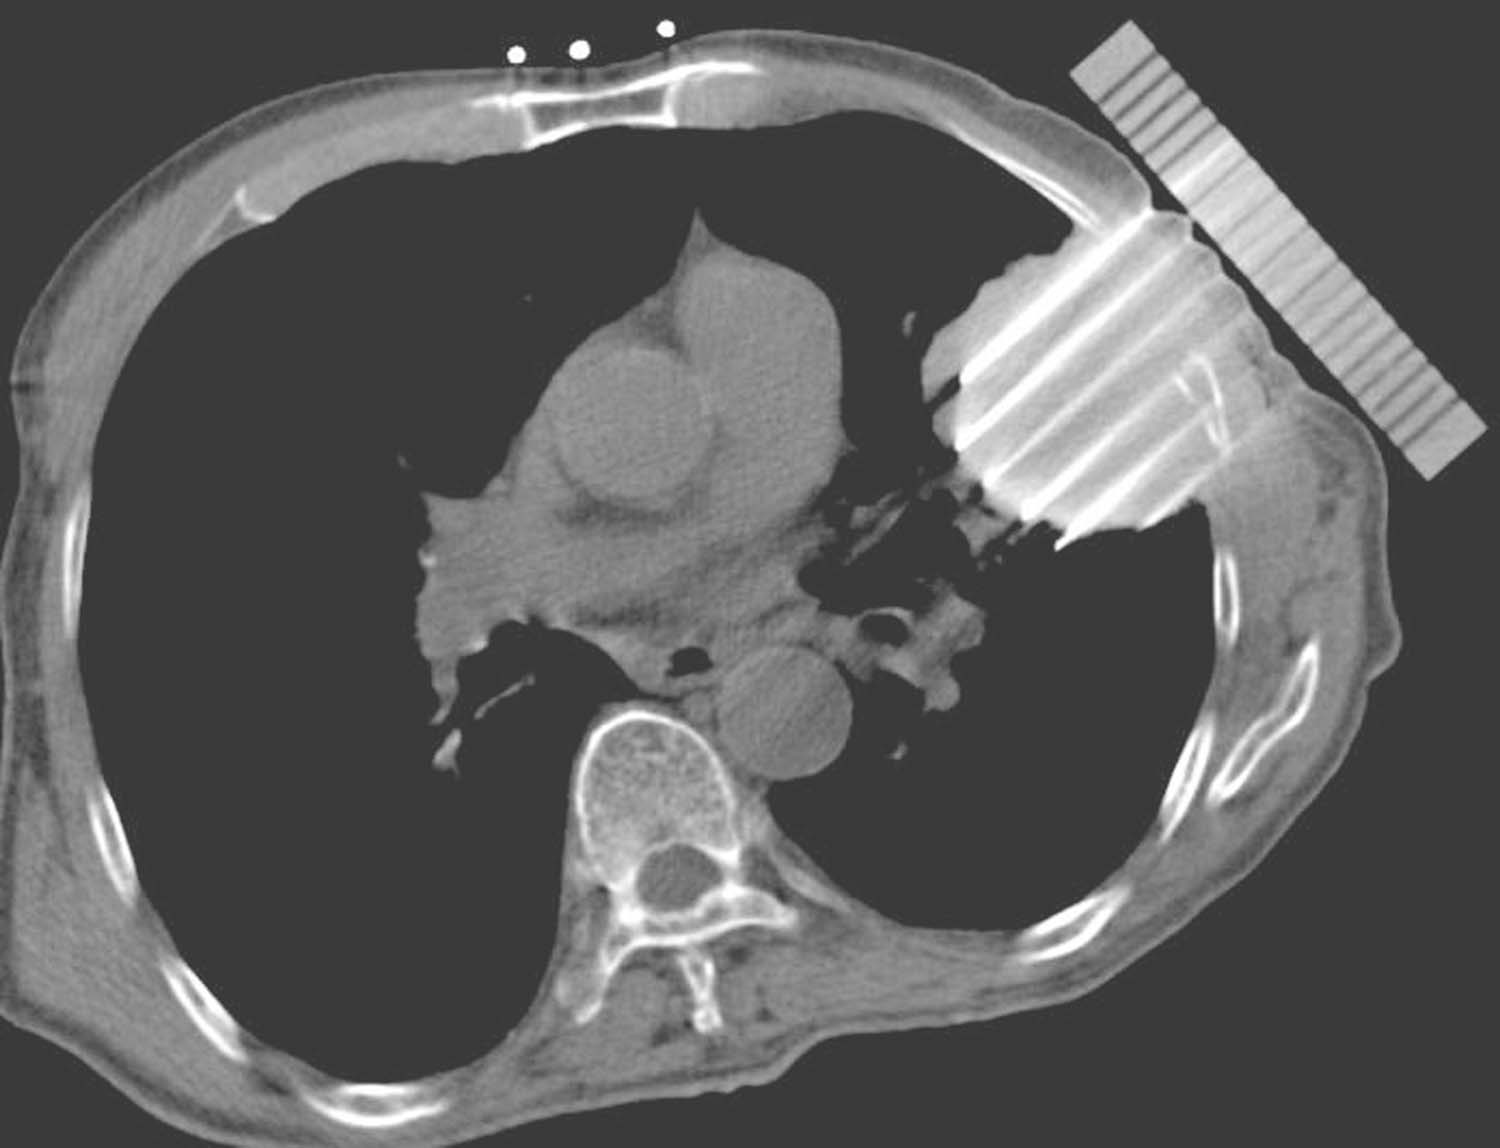

例2 女性,76岁,左肺周围型腺癌,T4N0M0,2017年10月12日行共面模板引导放射性粒子植入术(图4-3-8~图4-3-13)。

图4-3-8 术前针道设计

图4-3-9 术前针道分布三维重建图

图4-3-10 共面模板引导,一次性完成所有层面进针

图4-3-11 术后等剂量分布图

图4-3-12 术后粒子分布三维重建图

图4-3-13 术后7个月复查,病灶明显缩小,疗效部分缓解